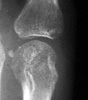

Symmetric well-circumscribed marginal erosions are seen at the involved articular

surfaces. Uncalcified soft tissue nodules and the absence of peri-articular

osteoporosis are additional radiographic features of multicentric reticulohistiocytosis.

Radiographic findings in multicentric reticulohistiocytosis are different

than those in rheumatoid arthritis since there is involvement of the joints

distally. Multicentric reticulohistiocytosis can also be differentiated from

other arthritides due to the absence of juxtaarticular osteoporosis and periosteal

reaction. The erosive pattern seen in gout and psoriatic arthritis is unlike

multicentric reticulohistiocytosis due to their asymmetric distribution. Furthermore,

calcified soft tissue nodules and overhanging edges are findings in gout which

are not seen in multicentric reticulohistiocytosis.